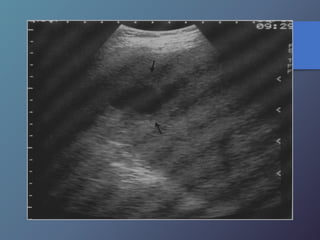

MT hipoecoicas:

• Son hipovasculares.

• Origen CA de mamas, pulmón, páncreas y esófago.

• Los linfomas hepáticos pueden manifestarse en masas

hipoecoicas, o difusas difíciles de diferenciar por ecografía

o TC.